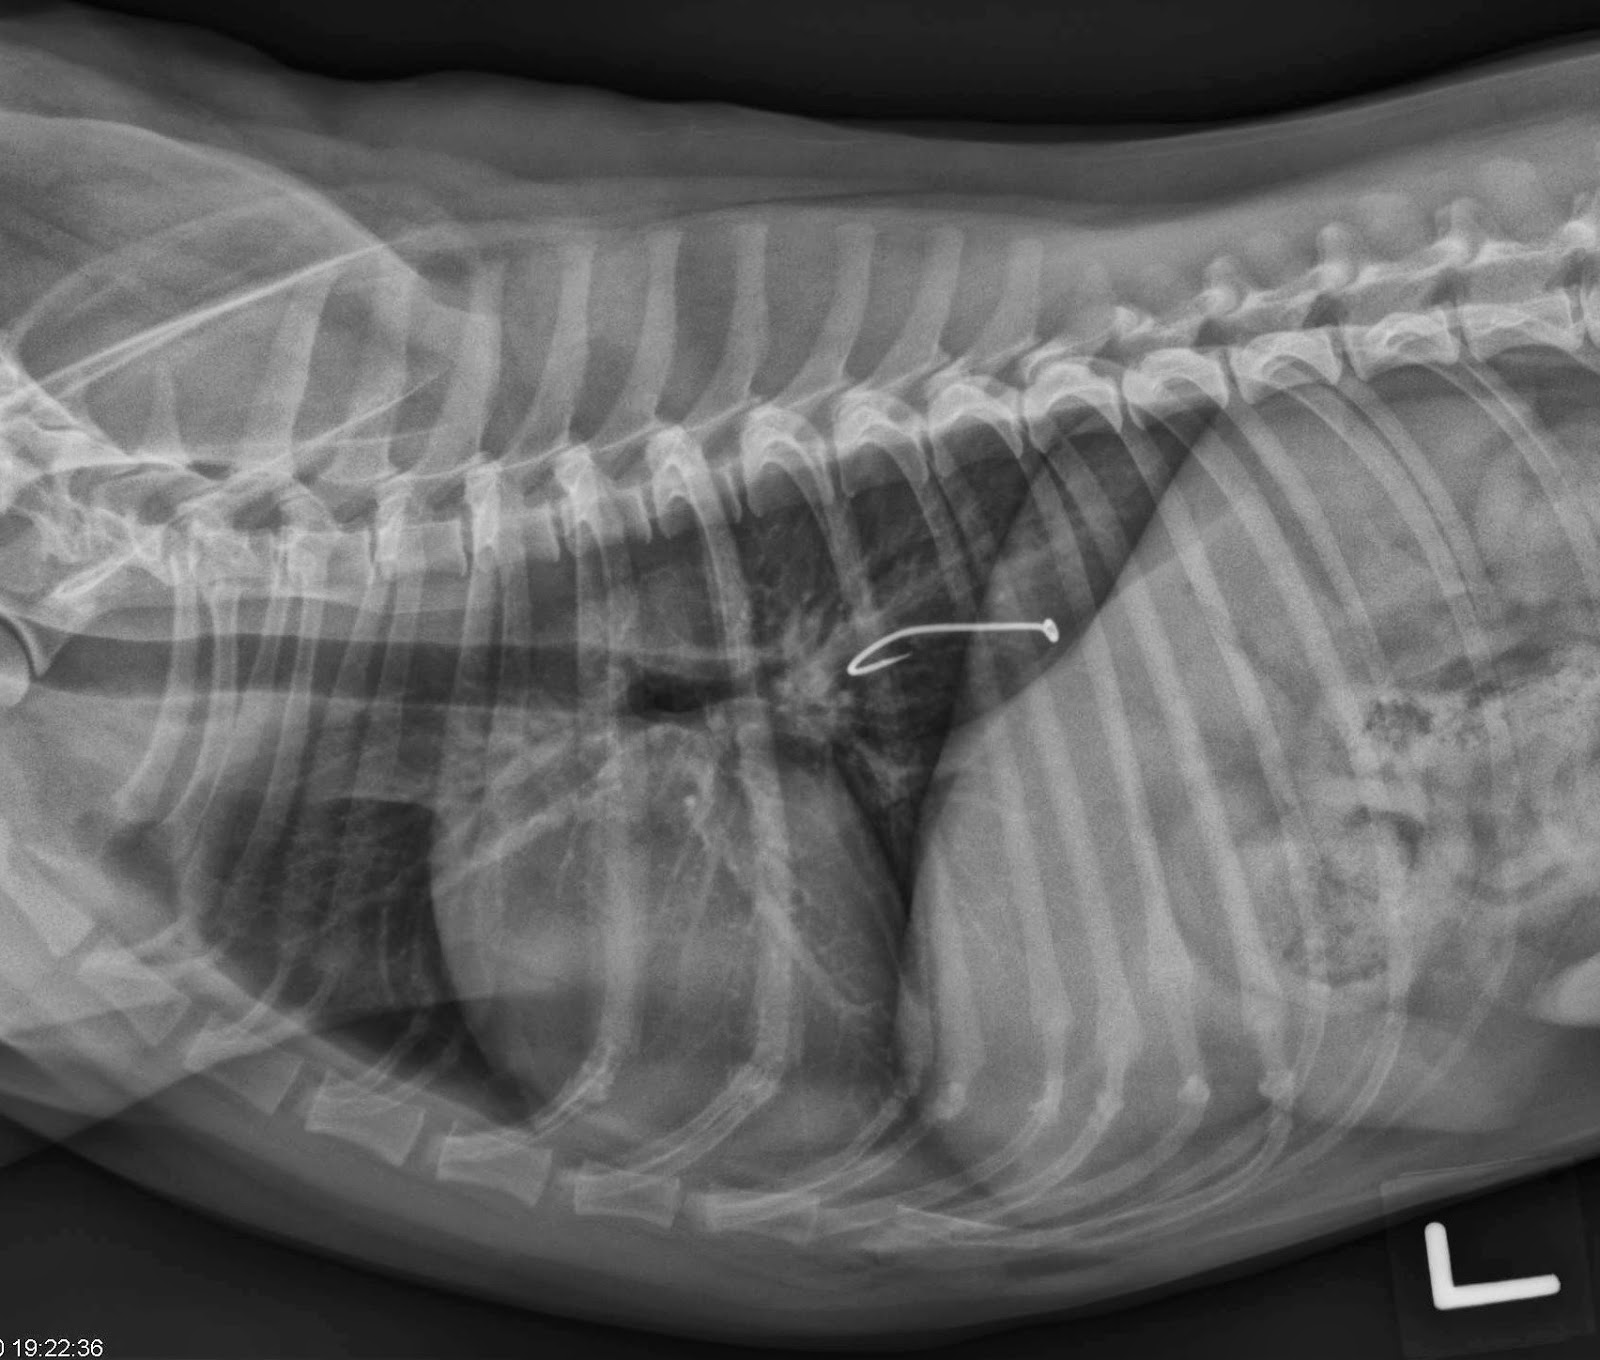

That being said, there are a few benefits. Both raw and cooked fish bones pose a risk to cats. No, cats should not eat salmon bones. While cats are carnivores and can consume bones in their natural diet, cooked salmon bones can be dangerous for cats. There is no short yes or no answer as to whether cats can eat fish bones. Fish heads and tails can be dangerous to cats because they can contain sharp bones that can puncture the cat’s digestive system. When fish bones are not chewed and swallowed whole, they can get stuck in your cat’s mouth, throat, esophagus, or anywhere in their. The fish bones, like the other bones (e.g. When pondering the question, “can fish bones kill a cat?” the unfortunate answer is, yes, they can. Can fish bones kill a cat?

Can a Cat Eat Fish Bone (& Fish to Avoid) Whiskerful Life Can Fish Bones Kill A Cat When fish bones are not chewed and swallowed whole, they can get stuck in your cat’s mouth, throat, esophagus, or anywhere in their. Can fish bones kill a cat? Unfortunately, this is quite possible. The fish bones, like the other bones (e.g. The sharp edges of fish bones. Fish heads and tails can be dangerous to cats because they can. Can Fish Bones Kill A Cat.